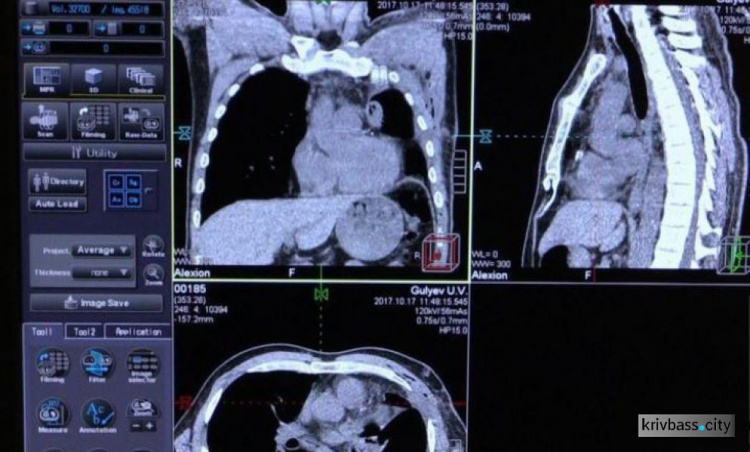

Жители Кривого Рога смогут обследоваться на заболевание туберкулёзом с помощью нового томографа, передаёт krivbass.city.

В противотуберкулезном диспансере №2, который находится в Терновском районе, появился новый компьютерный томограф. Это медучреждение обслуживает не только Кривой Рог и его население, но и сельские районы.

Данный прибор помогает обнаружить микрочастицы палочки Коха и распознать их среди других заболеваний лёгких. Благодаря этому врачи смогут выявлять туберкулёз у пациентов ещё на ранних стадиях, что будет способствовать быстрому выздоровлению больных.

На покупку компьютерного томографа потратили почти три миллиона гривен. Средства выделили из городского и областного бюджетов. Всего в нашем городе четыре таких аппаратов.